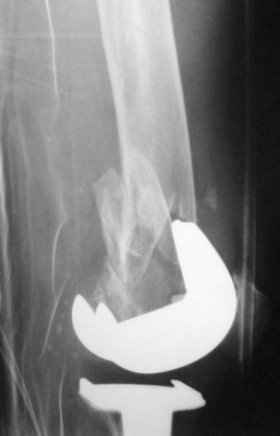

My preference would be to rigidly fix the fracture internally. I just feel that it may not be possible given the very porotic nature of the bone distal to the fracture (I am re-sending the lateral x-ray which really concerns me).

I doubt if I could lock a nail (either antegrade or retrograde) distal to the fracture which extends virtually to the implant. I have similar concerns about plate fixation. Has anyone got a reasonable volume of experience with this type of fracture?